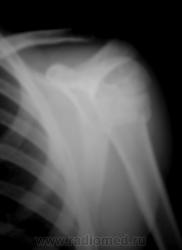

Да, дети разные.

Это у меня нижняя группа снимков не загрузилась - решил верхние - двух человек...

В обоих случаях перелом хирургической шейки плечевой кости. А почему только в одной проекции? Мы всегда снимаем в двух - в прямой и аксиальной.